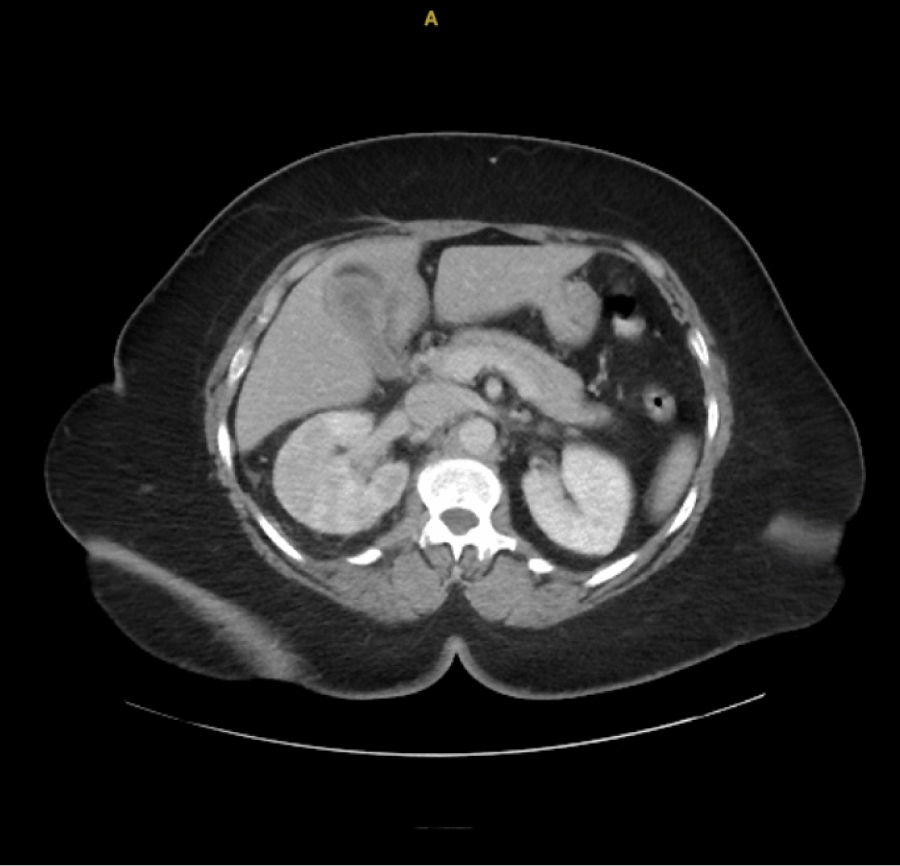

A 64-year-old woman with hypertension and gastroesophageal reflux disease presented with abdominal pain, nausea, vomiting, and fevers for 3 days. On admission, she was tachycardic (HR 110), with blood pressure 133/79 mmHg and temperature 38°C. Laboratory evaluation revealed leukocytosis (WBC 15.5 ×103/µL), lactic acidosis, and thrombocytopenia. Urinalysis was positive for infection with 20 WBC, 10-20 RBCs and Positive Leukocyte Esterase and Nitrites. CT abdomen and pelvis revealed an 8 × 4 mm proximal right ureteral stone with right-sided Uretral Stone and perinephric stranding (Figures 1 and 2).

Figure 1: CT abdomen/pelvis (axial) showing patchy right renal cortical enhancement and perinephric edema consistent with obstructive pyelonephritis. View Figure 1

Figure 2: CT abdomen/pelvis (coronal) demonstrating an 8 × 4 mm right proximal ureteral stone with right-sided hydroureter and perinephric stranding. View Figure 2